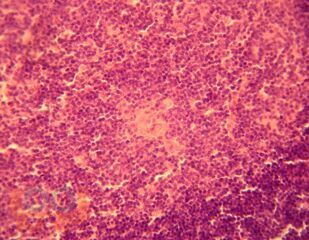

Тимус (морфология вилочковой железы при моторной депривации)

Монография посвящена результатам исследования возрастной морфологии тимуса в условиях воздействия дозированной гиподинамии и гипокинезии, которые можно использовать в различных разделах школьной гигиены, педиатрии, иммунологии, возрастной морфологии, в спортивной медицине.

Книга предназначена для анатомов, гистологов, физиологов и может быть полезна для молодых ученых в области биологических и медицинских наук.